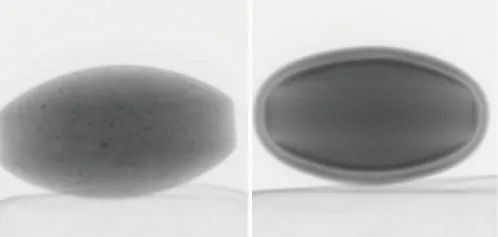

在本例中,觀察到兩種具有不同結構的片劑(片劑A和B)(圖2)。片劑的透視圖像如圖3所示。

片劑A (左) 片劑B(右)

圖3 片劑透視圖